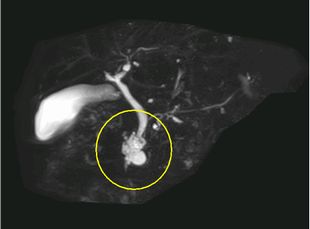

MRCP MIP画像(膵頭部嚢胞)

MRI 横断像(膵頭部嚢胞)